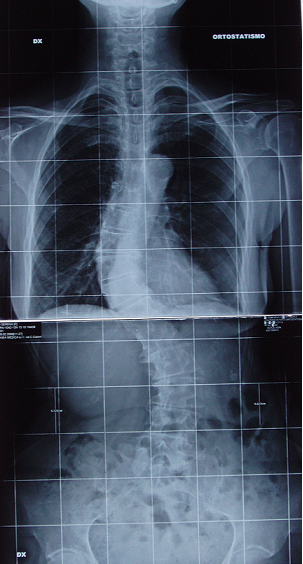

Solette propriocettive nella scoliosi idiopatica lieve.